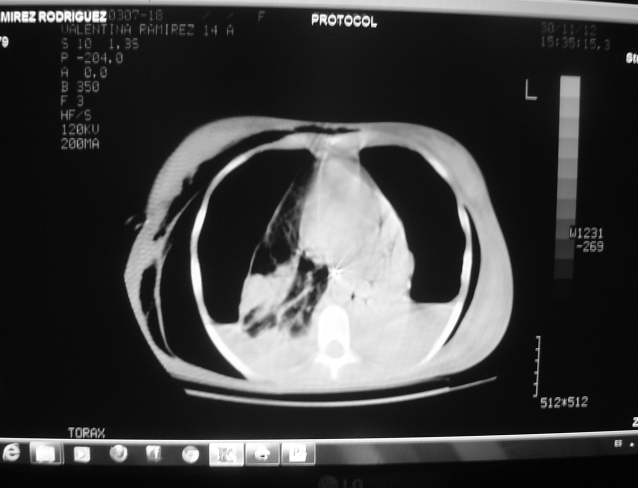

El amplio espectro clínico de la neumonía adquirida en comunidad genera problemas para su diagnóstico. La neumonía producida por Staphylococcus aureus es conocida como necrotizante, de rápida evolución y alta mortalidad. Se describe el caso de una mujer de 14 años con neumonía necrotizante por S. aureus resistente, evolucionó rápidamente a insuficiencia respiratoria requirió ventilación mecánica presento bacteriemia, empiema, neumatoceles, neumotórax bilateral persistente con fistulas broncopleurales que requirieron corrección quirúrgica. No se detectaron factores de riesgo. Los cultivos en sangre, líquido pleural, lavado traqueal fueron positivos y el tratamiento fue exitoso.